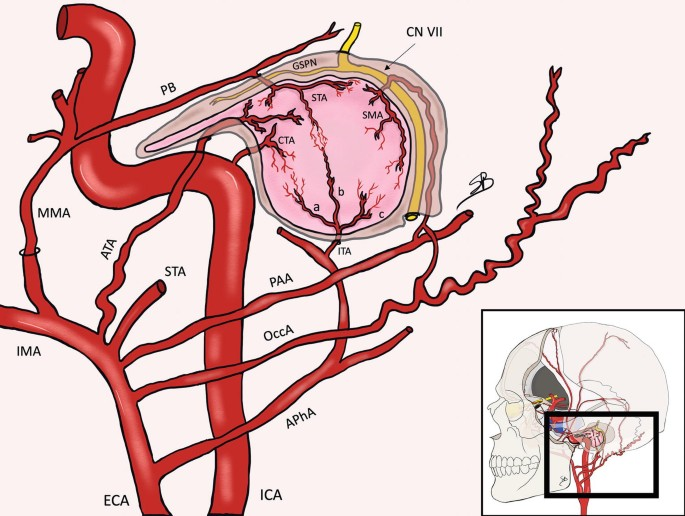

Maxillary a.

- Mandibular part

- Pterygoid part

- Pterygopalatine part

Info

Maxillary a.通過pterygoid muscle淺層,穿入pterygopalatine fossa

First part

- Ant. tympanic a.

- 進入 tympanic cavity,供應 tympanic membrane

- Middle meningeal

- 被Auriculotemporal n. 環繞

Second part

皆有(CN V3)伴行,除了Buccal n.為sensory,其為motor

- Ant./post. deep temporal a.

- Buccal a.

- Masseteric a.

- Pterygoid a.

Third part

皆有sensory 伴行,穿入pterygopalatine fossa

- Sphenopalatine a.

- 最終分支,進入 Sphenopalatine foramen,支配鼻竇

- Vidian a.

- Vidian n.

- maxillary tuberosity

- on alveolar bone